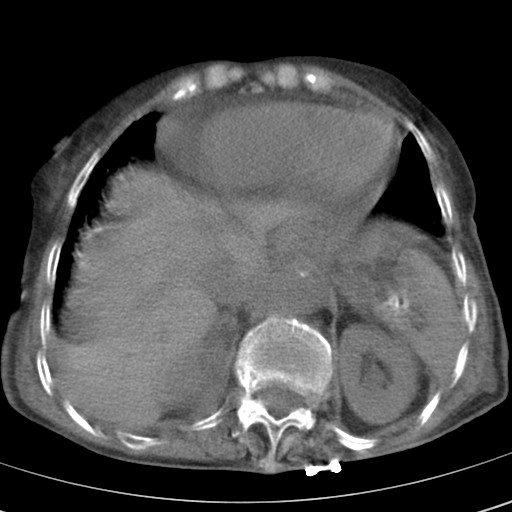

女,93岁,摔伤后检查。

食管裂孔疝

创伤性湿肺,双侧胸腔积液。可能有食管裂孔疝,进一步检查。骨折有无根据自己的机器及片子再仔细看吧。

右侧锁骨\\肩胛骨骨折、右侧湿肺,心功能不全伴双侧胸腔积液,右下肺膨胀不全,左膈破裂或食管裂孔疝,冠脉钙化,心包少量积液,请上传骨窗.

右肺炎症,心功能不全伴双侧胸腔积液,右下肺膨胀不全,食管裂孔疝,冠脉钙化,心包少量积液,左侧肋骨骨折,右肩甲骨粉碎性骨折。93岁,高寿哇!